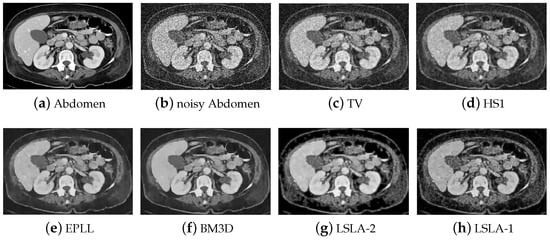

| Image | Wall | Abdomen | ||||||

| Method | TV | PSNR | 20.70 | 18.19 | 16.80 | 22.57 | 20.06 | 18.50 |

| SSIM | 0.6521 | 0.5601 | 0.4978 | 0.5579 | 0.4940 | 0.4697 | ||

| HS | PSNR | 21.33 | 18.54 | 17.03 | 23.29 | 20.52 | 18.77 | |

| SSIM | 0.7043 | 0.5975 | 0.5460 | 0.6384 | 0.5592 | 0.5300 | ||

| EPLL | PSNR | 21.36 | 18.38 | 16.76 | 23.51 | 20.64 | 18.84 | |

| SSIM | 0.7254 | 0.6254 | 0.5698 | 0.6517 | 0.5915 | 0.5440 | ||

| BM3D | PSNR | 21.97 | 19.04 | 17.42 | 24.14 | 21.26 | 19.50 | |

| SSIM | 0.7421 | 0.6410 | 0.5838 | 0.6700 | 0.6026 | 0.5603 | ||

| LSLA-2 | PSNR | 22.28 | 20.11 | 19.22 | 25.06 | 22.68 | 21.47 | |

| SSIM | 0.7598 | 0.6730 | 0.6477 | 0.7530 | 0.6680 | 0.6237 | ||

| LSLA-1 | PSNR | 22.51 | 20.31 | 19.12 | 24.97 | 22.72 | 21.37 | |

| SSIM | 0.7675 | 0.6736 | 0.6311 | 0.7462 | 0.6663 | 0.6096 | ||